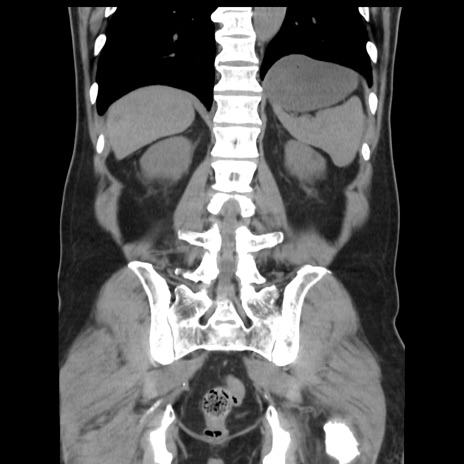

症例16(冠状断像)

【現病歴】 約1ヶ月前より間欠的に腹痛と嘔吐あり、当院消化器内科を受診したところCTで多発する肝臓のLDAを指摘され、精査中であった。以降は消化器症状は安定していたが、2日前より嘔気と腹痛があり、同日より排便・排ガスが消失した。改善認めず、 本日、救急外来を受診した。

横断像